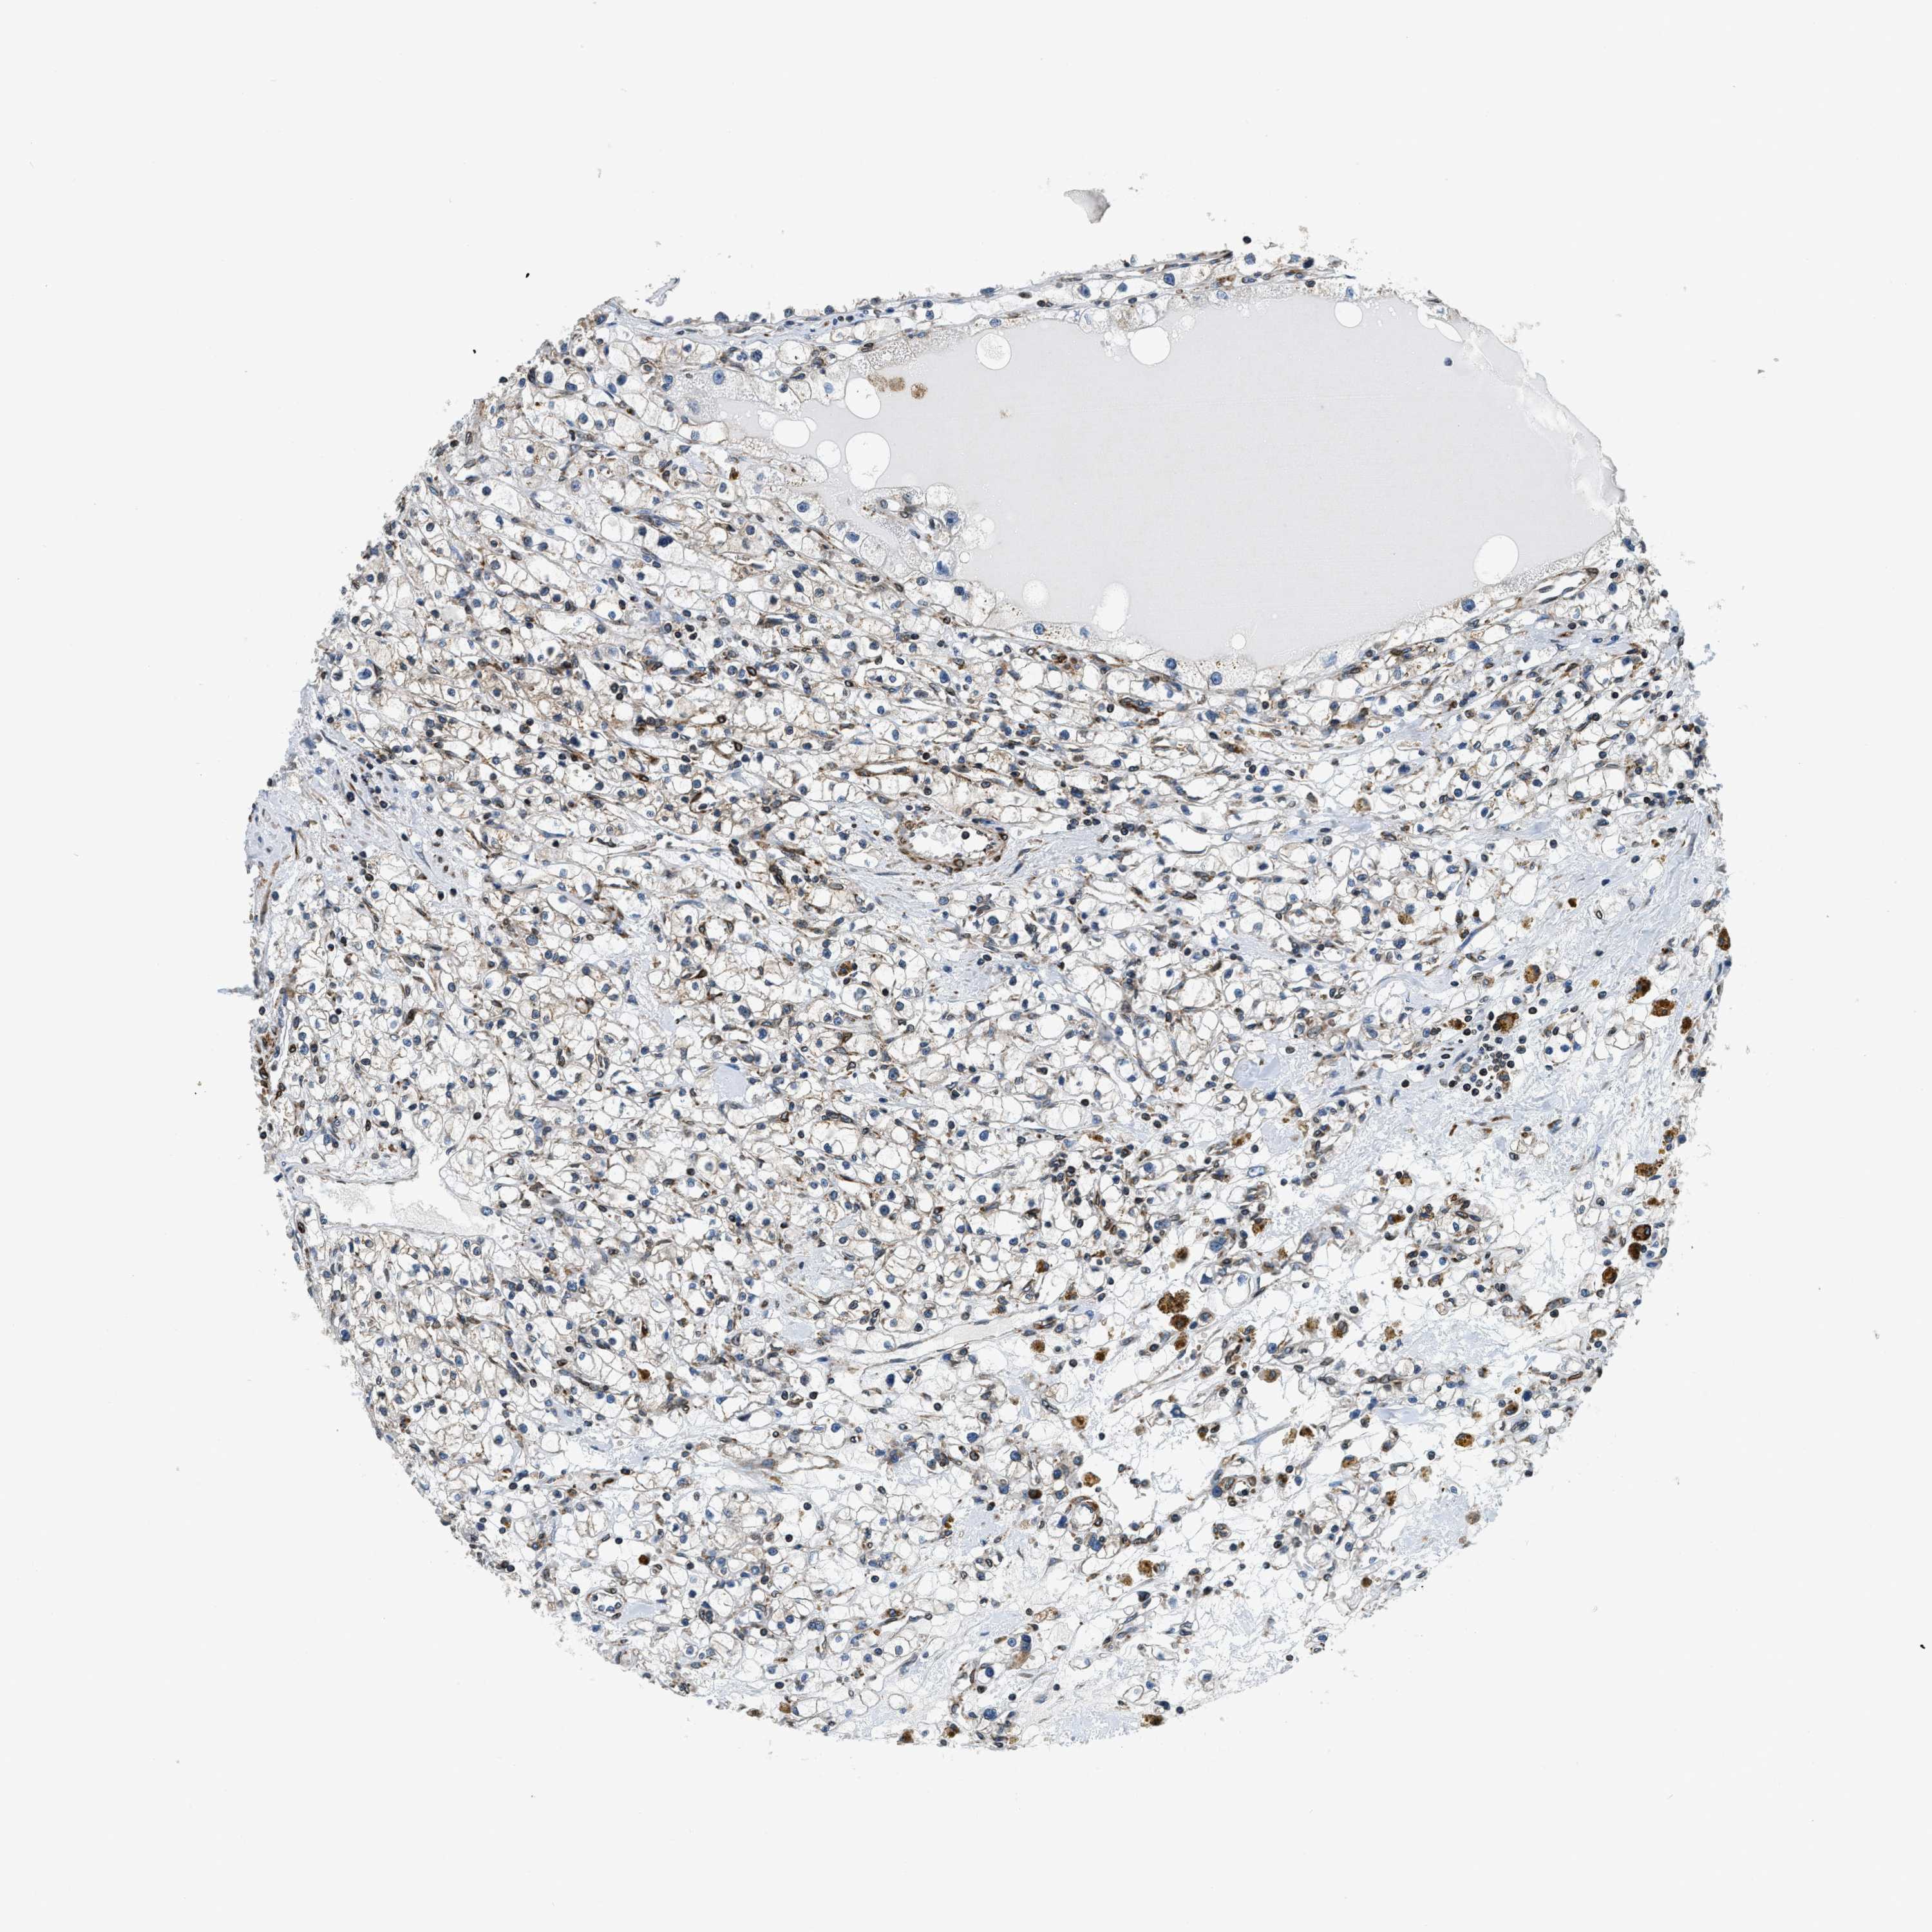

KIDNEY RENAL CLEAR CELL CARCINOMA (VALIDATION) - Interactive survival scatter ploti

The Survival Scatter plot shows the clinical status (i.e. dead or alive) for all individuals in the patient cohort, based on the same data that underlies the corresponding Kaplan-Meier plots. Patients that are alive at last time for follow-up are shown in blue and patients who have died during the study are shown in red.

The x-axis shows the expression levels (FPKM) of the investigated gene in the tumor tissue at the time of diagnosis. The y-axis shows the follow-up time after diagnosis (years). Both axes are complimented with kernel density curves demonstrating the data density over the axes. The top density plot shows the expression levels (FPKM) distribution among dead (red) and alive patients (blue). The right density plot shows the data density of the survived years of dead patients with high and low expression levels respectively, stratified using the cutoff indicated by the vertical dashed line through the Survival Scatter plot. This cutoff is automatically defined based on the FPKM cutoff that minimizes the p-score. The cutoff can be changed by dragging the vertical line or by entering a cutoff value in the square labeled "Current cut-off".

Under the Survival Scatter plot the p-score landscape (black curve; left axis) is shown together with dead median separation (red curve; right axis). Dead median separation is the difference in median mRNA expression between patients who have died with high and low expression, respectively. It is calculated as follows: median FPKM expression of dead patients with high expression - median FPKM expression of dead patients with low expression. This is intended to aid the user in visually exploring custom cutoffs and the associated p-scores and dead median separation.

Individual patient data is displayed and can be filtered by clicking on one or more of the category buttons on the top of the page. Categories describing expression level and patient information include: high, low, alive, dead, female, male and tumor stages. The scale of the x-axis can be toggled between linear and log-scale by clicking on the "x log" button. Mouse-over function shows TCGA ID, patient information and mRNA expression (FPKM) for each patient.

& Survival analysisi

Kaplan-Meier plots summarize results from analysis of correlation between mRNA expression level and patient survival. Patients were divided based on level of expression into one of the two groups "low" (under cut off) or "high" (over cut off). X-axis shows time for survival (years) and y-axis shows the probability of survival, where 1.0 corresponds to 100 percent.

CDS2 is validated prognostic, high expression is favorable in Kidney Renal Clear Cell Carcinoma (validation)

Best expression cut offi

Based on the FPKM value of each gene, patients were classified into two groups and association between prognosis (survival) and gene expression (FPKM) was examined. The best expression cut-off refers the FPKM value that yields maximal difference with regard to survival between the two groups at the lowest log-rank P-value. Best expression cut-off was selected based on survival analysis .

When clicking on this number, the vertical dashed line indicating cut-off, the interactive survival plot, and the Kaplan-Meier curve will be adjusted to show results based on the best expression cut-off.

: 22.2

TCGA RNA samplesi

RNA-seq data is reported as average FPKM (number Fragments Per Kilobase of exon per Million reads), generated by the The Cancer Genome Atlas (TCGA) .

Normal distribution across the dataset is visualized with box plots, shown as median and 25th and 75th percentiles. Points are displayed as outliers if they are above or below 1.5 times the interquartile range. FPKM values of the individual samples are presented next to the box plot.

Average pTPM 18.0

Number of samples 100